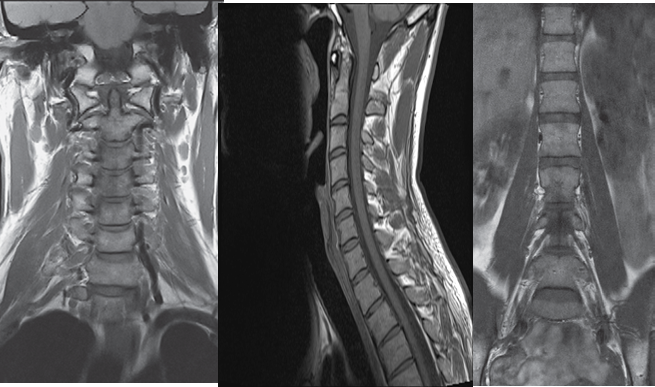

The gold standard of imaging for spinal disorders

Can identify abnormalities of bone, discs, muscles, ligaments and spinal cord

Intravenous contrast is sometimes administered to better visualize certain structures or abnormalities